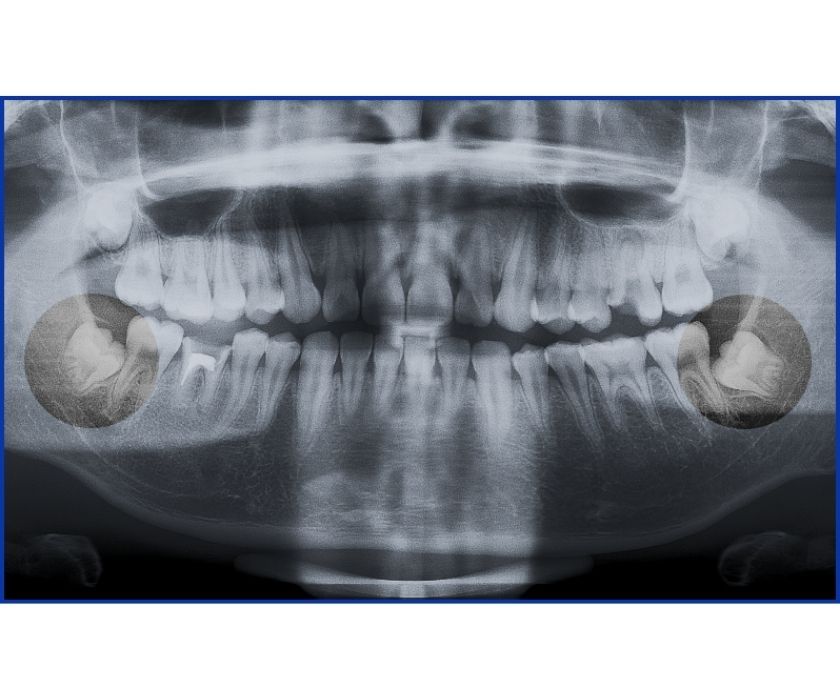

Hình chụp x-quang răng khôn mọc kẹt

- Trên phim X-quang, thấy răng khôn mọc lệch 45–90 độ so với răng số 7.

- Bác sĩ phát hiện trên phim X-quang răng khôn mọc kẹt một phần hoặc mọc ngầm ngang.